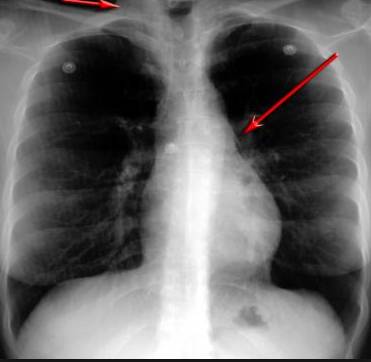

并且,因為呼吸系統(tǒng)結(jié)構(gòu)復(fù)雜,在體檢時醫(yī)生很難通過一種檢測手段,判定早期患者的病情。

使用這臺掃描儀,將直接把器官變成3D圖形!細微的毛細血管,幾毫米大的肺泡和支氣管,都將能看的一清二楚!

你的每一個氣泡,每一段支氣管,哪兒有病變都清清楚楚的將展示在醫(yī)生面前!

也就是說在一切都還沒開始惡化前,把這些有問題的器官組織都暴露的一清二楚:

不同于CT掃描,需要從同一角度,拍下無數(shù)張器官二維圖,從而搭建3D器官結(jié)構(gòu)圖那般費時費力。

4D掃描儀將直接從不同角度,同時對人體器官進行掃描,然后通過計算機算法進行快速成像。CT需要花幾小時才能完成的工作,

4D掃描將在幾秒內(nèi)完成!

沒有這項新技術(shù),醫(yī)生在做體檢的時候,很難通過一種測試斷定一個人是否有呼吸系統(tǒng)疾病。

可是現(xiàn)在他們不但能看到整個肺部的3維結(jié)構(gòu)圖。還能看到空氣進入人體后的所有微小變動!